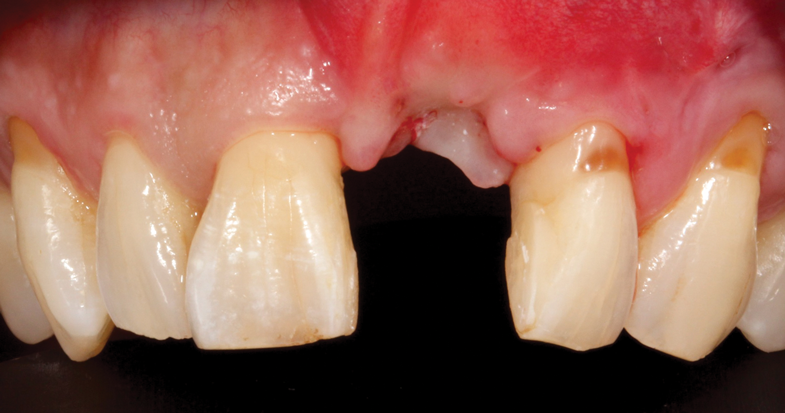

(45.) A patient presented for the replacement of the maxillary left central incisor with a bonded pontic made from the natural tooth, which was removed.

Figure 45